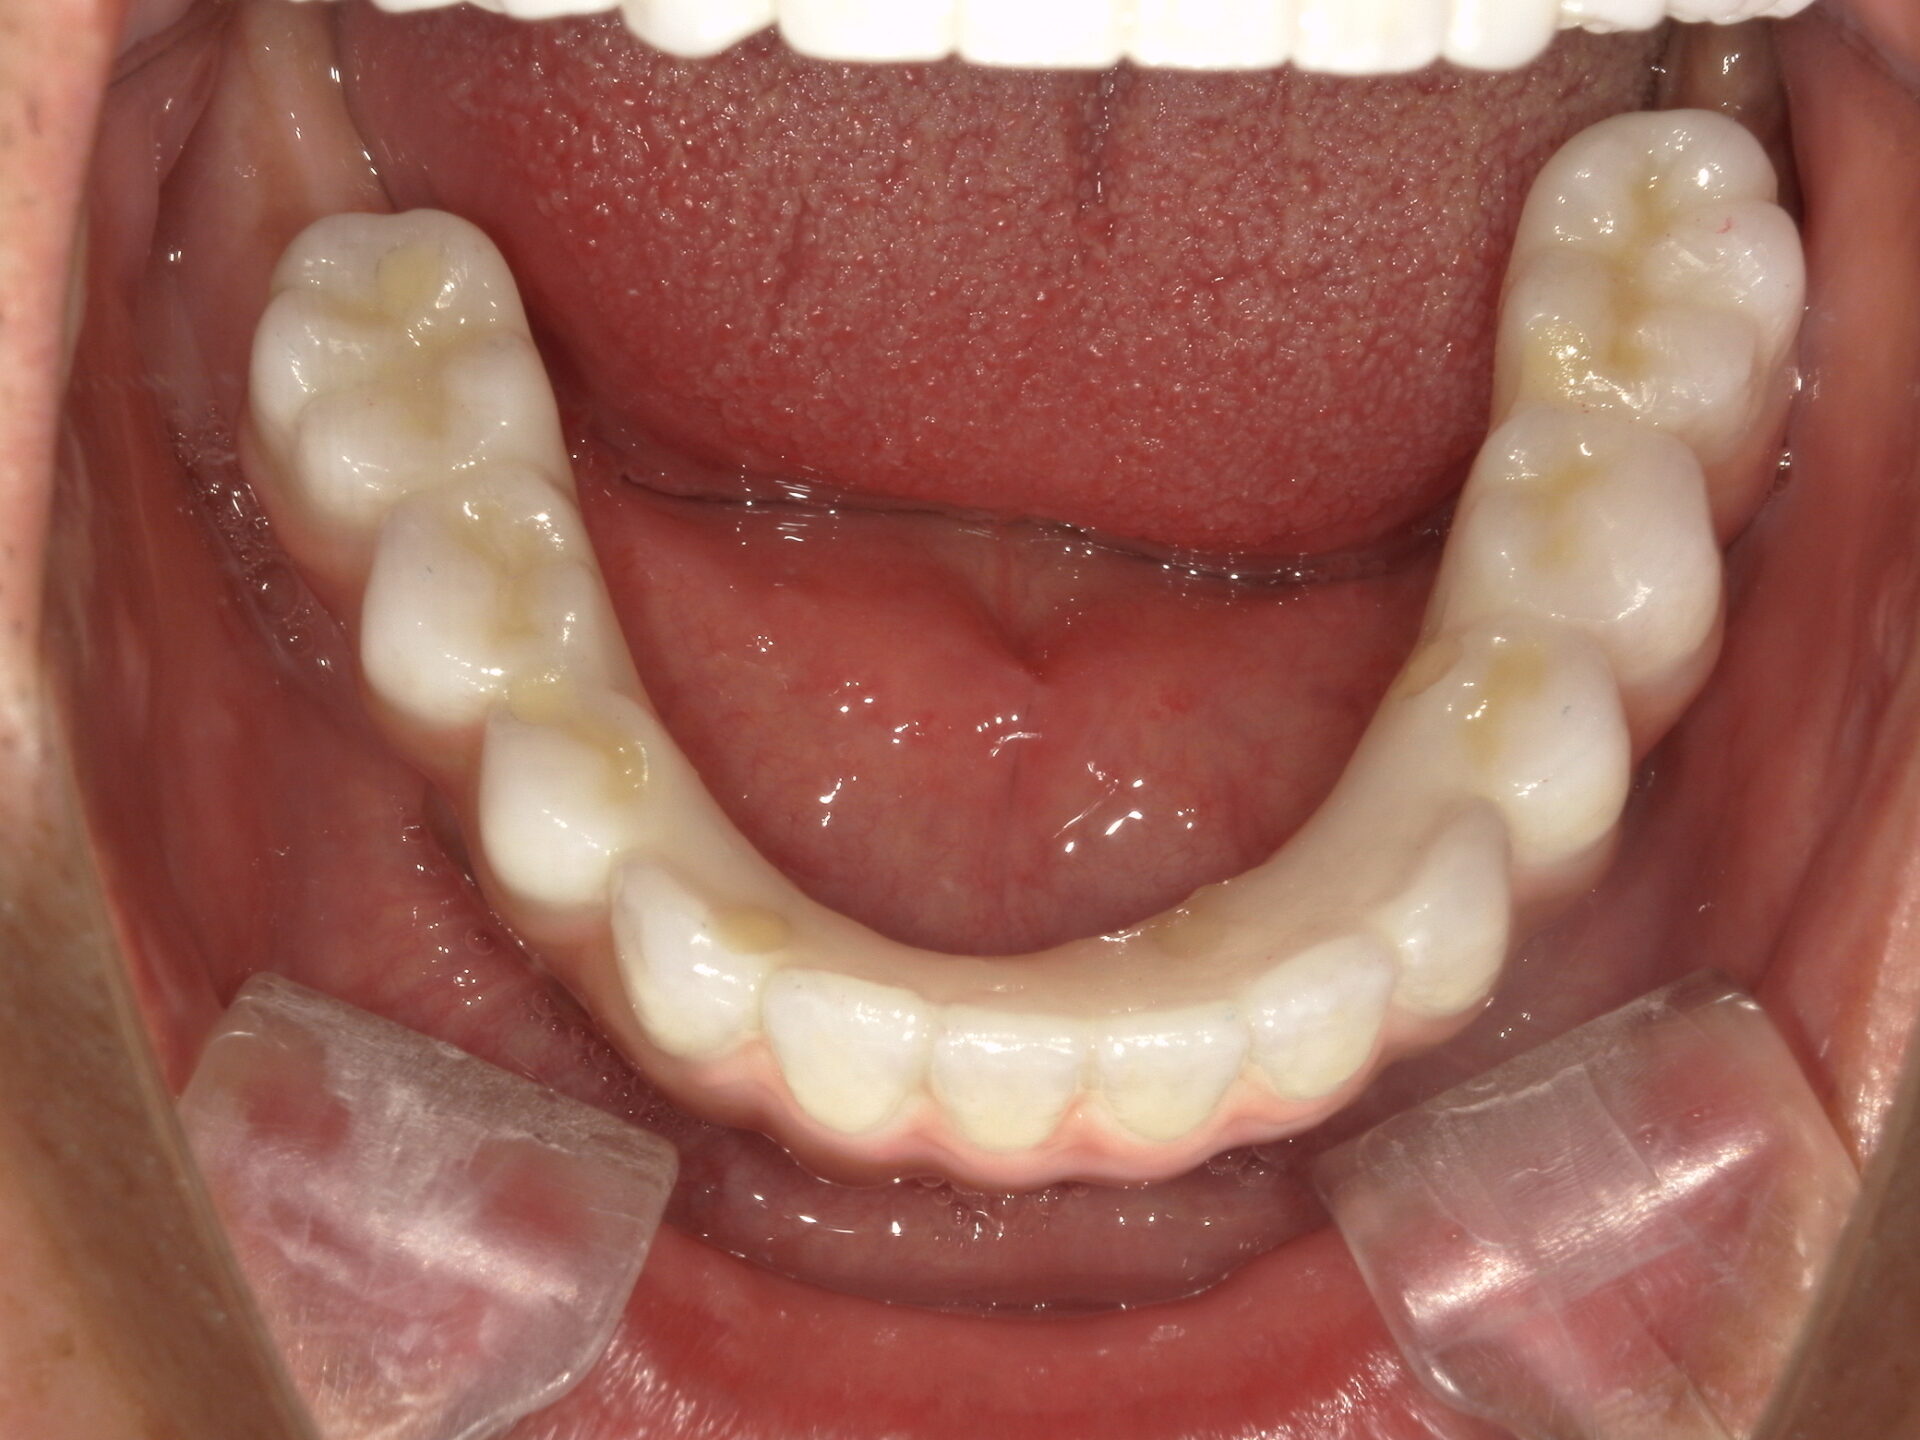

before

after

患者さんの年齢 50代 男性 症状 何も噛めない 治療内容 インプラント治療(オールオン4) 費用 費用900万(税抜) 治療期間・回数 治療期間2年・通院回数12回 メリット なんでも噛めるようになる 見た目が綺麗 デメリット・リスク 骨造成などで費用が増える場合がある - インプラント治療